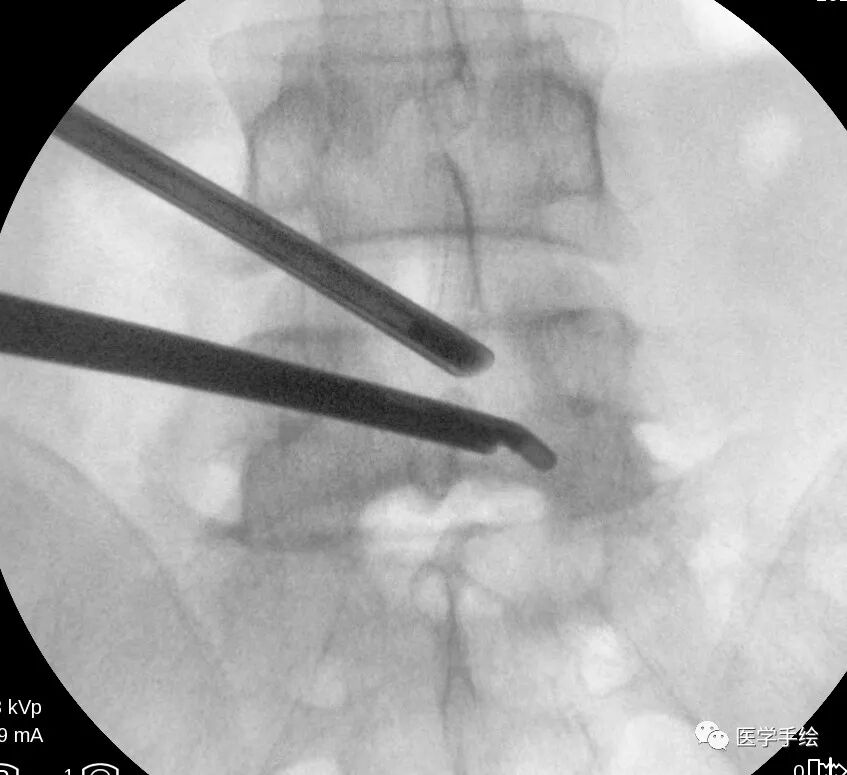

为了避免translamina入路棘突磨穿风险,我们尝试先显露对侧椎板上缘明确对侧椎板方向。

在对侧椎板上缘指示方向下行translamina操作,直至显露对侧黄韧带上缘和椎间孔区域黄韧带

经translamina入路探及下位椎弓孔区域的范围

看到下位椎间孔区域的上关节突尖